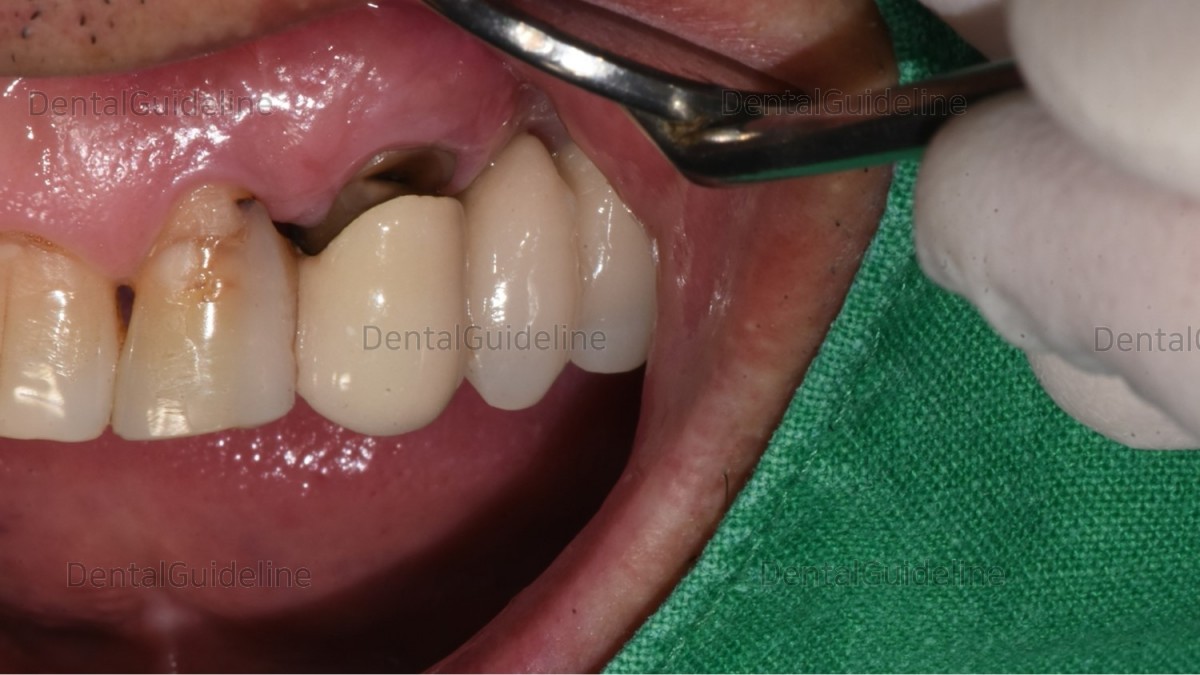

<GCkbs> Recurrent fistula and intermittent dull pain in the apical lesion of the canine.

flap opening, lesion exposure.